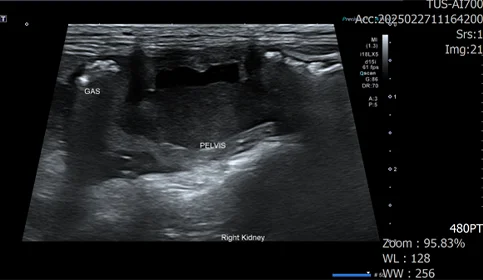

우측 신장 주변부 가스, 복수, 신장의 형태 변화, 신우의 확장, 요관 확장 확인

신우내 저류하는 액체 천자 진행, 점액성 농이 다수 확인

정밀 검사 결과, 신장 주변 가스, 복수, 신장 파열이 확인되었습니다.

세균성 신우신염으로 인한 신장 파열이 발생, 그로 인한 이차적인 복막염으로 진행되는 상태입니다.